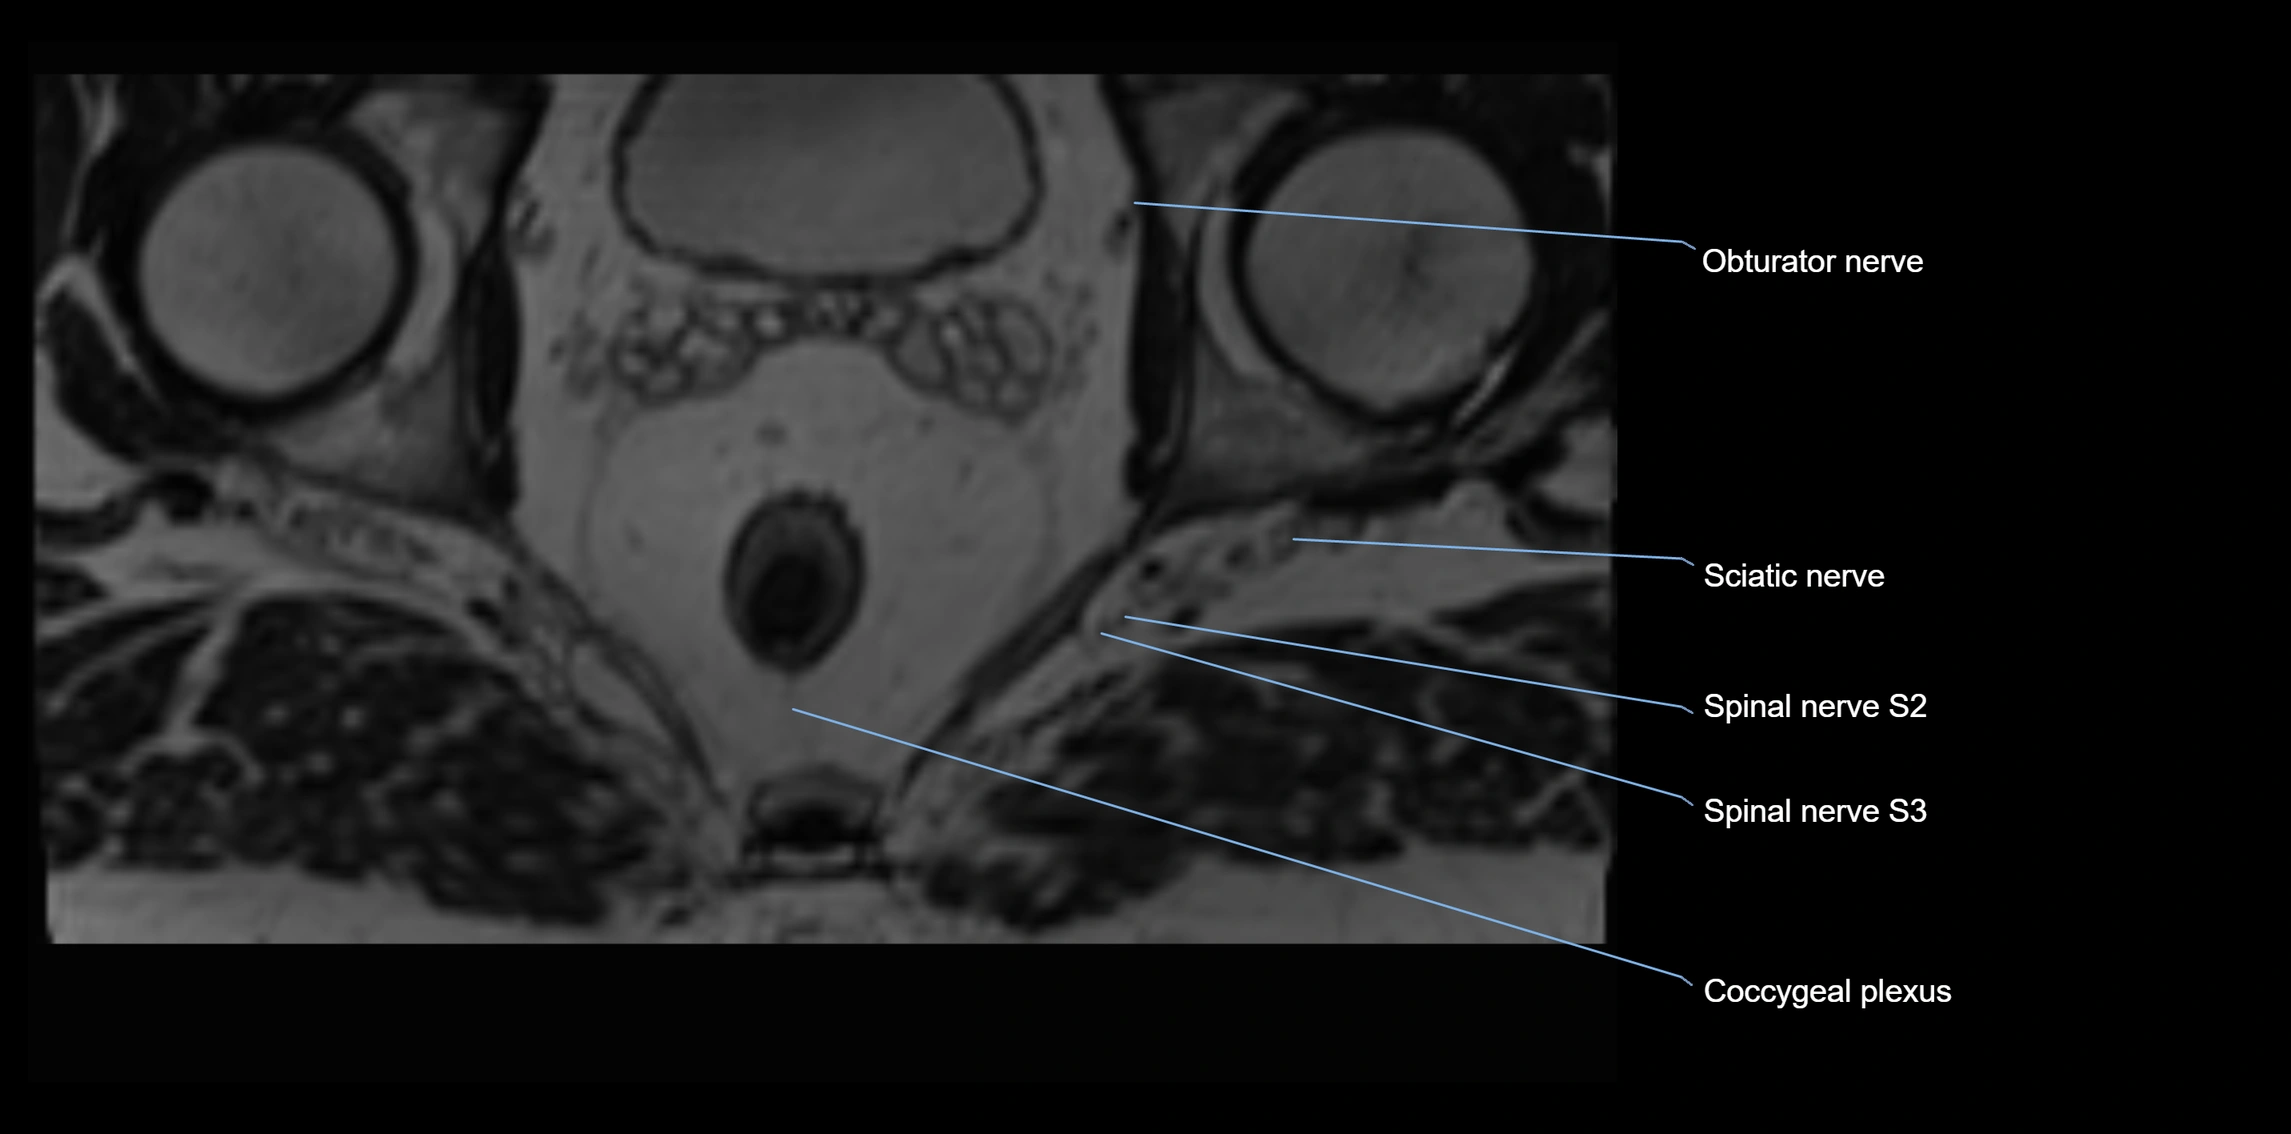

MRI image

image